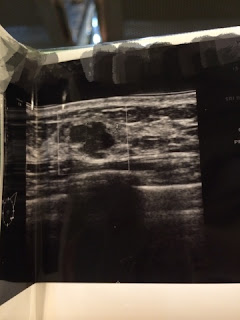

(That was my breast lump)

(That was my left ovarian cyst)